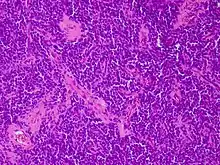

Los tumores vaginales son neoplasias que se encuentran en la vagina. Pueden ser benignos o malignos.[1] Una neoplasia es un crecimiento anormal de tejido que generalmente forma una masa de tejido.[2][3][4] Las neoplasias vaginales pueden ser sólidas, quísticas o de tipo mixto.[5]

Los cánceres vaginales surgen del tejido vaginal, y los sarcomas vaginales se desarrollan a partir de hueso, cartílago, grasa, músculo, vasos sanguíneos u otro tejido conjuntivo o de soporte.[6][7] Los tumores en la vagina también pueden ser metástasis (tejido maligno que se ha diseminado a la vagina desde otras partes del cuerpo).[8][7] El cáncer que se diseminó desde el colon, vejiga y estómago es mucho más común que el cáncer que se origina en la vagina.[9] Algunos tumores benignos pueden progresar hasta convertirse en tumores malignos, como los cánceres vaginales.[10][11] Algunos tumores neoplásicos de la vagina son lo suficientemente raros como para describirse solo en estudios de casos.[3]

Los signos y síntomas pueden incluir una sensación de presión, relaciones sexuales dolorosas o sangrado.[12] La mayoría de los tumores vaginales se localizan durante un examen pélvico. La ecografía, tomografía computarizada y resonancia magnética se utilizan para establecer la ubicación y la presencia o ausencia de líquido en un tumor.[13][14] La biopsia proporciona un diagnóstico más definitivo.[15]